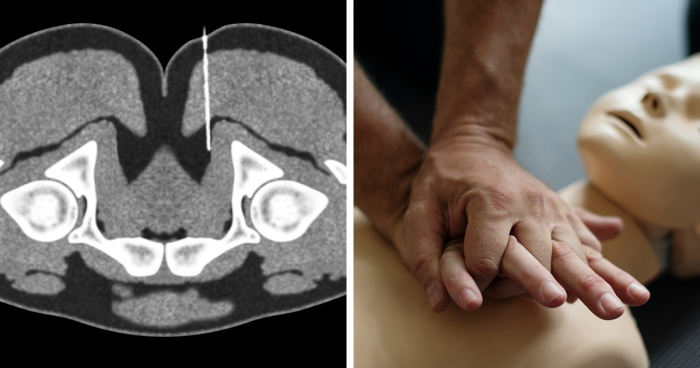

When it comes to what makes the perfect cursed image, The Next Web says there’s a bit of a formula that many on the internet have managed to perfect. First, they note that the best ones actually require skill to create. The subject or photographer must be dedicated to creating an image that evokes emotion and might even require physical skill.

The Next Web notes that the “building blocks” of the cursed aesthetic include: defamiliarization, high contrast photography (often with flash), and sometimes even “recasting food as a reminder of mortality and lack of agency.” The image must include objects that we all know and love presented in a way that makes them feel foreign. The photo itself also shouldn’t be pleasant to look at. If it’s been taken with flash, the subjects might look much harsher than they would in reality.

As for why we can’t look away from these unsettling cursed images, Francis McAndrew, a professor of psychology at Knox College, told Paper his theory. “We are drawn to 'cursed images' because they somehow present us with a nagging ambiguity," he shared. "Things that we cannot quickly make sense of trouble us and hold our attention, and we feel compelled to analyze them until we feel as if we understand them."

“The cursed image exists as a direct challenge to an Internet flooded with deepfakes and photoshopped candids, positing a reality that is far stranger than anything we could fabricate by ourselves,” Moen continued. “The cursed image feels like proof that we've crossed over into an alternate dimension, a Twilight Zone populated by the mundane. The cursed image haunts us and, scarier still, we like it.”